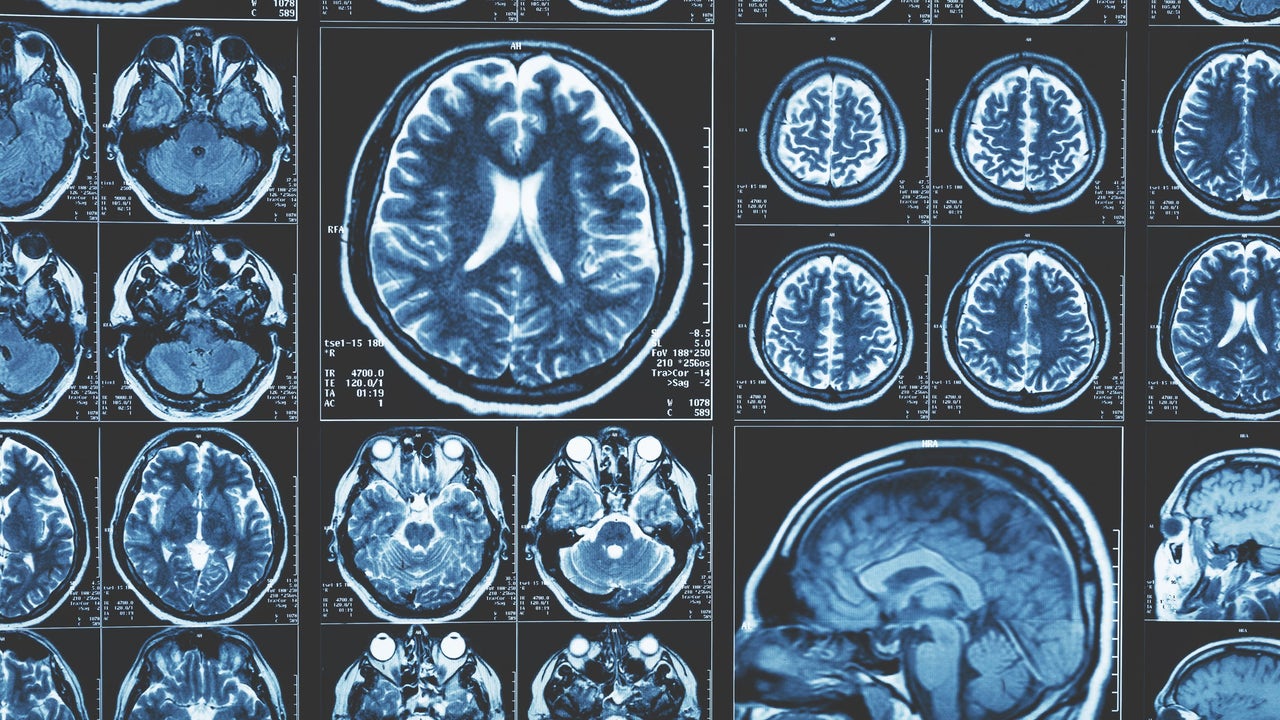

Este proceso biológico ya había sido relacionado antes con otras enfermedades neuronales como la Esclerosis Múltiple, la Esclerosis Lateral Amiotrófica, el Alzheimer o el Parkinson...